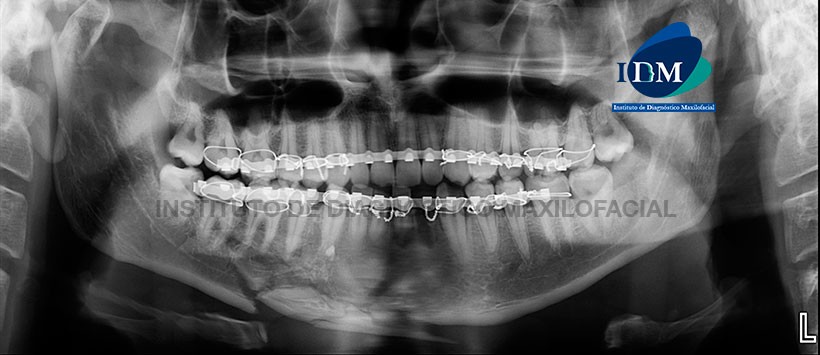

Paciente de sexo masculino 26 años de edad acude al Instituto de Diagnóstico de Maxilofacial para control post tratamiento.

A la evaluación de la radiografía panorámica se visualizan fracturas con desplazamiento de ambos condilos mandibulares, neumatizacion de ambos senos maxilares, múltiples trazos de fractura a nivel de zona sinfisiaria y parasinfisiaria con desplazamiento de fragmentos, lecho alveolar de la pieza 38, arco de fijación bimaxilar y ausencia de la pieza 32. (Figura 1)